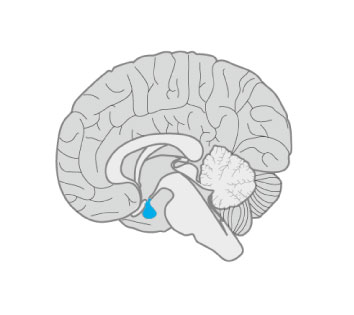

Ce syndrome rare est caractérisé par une hypophyse postérieure absente ou ectopique, une tige interrompue et une hypoplasie hypophysaire antérieure…